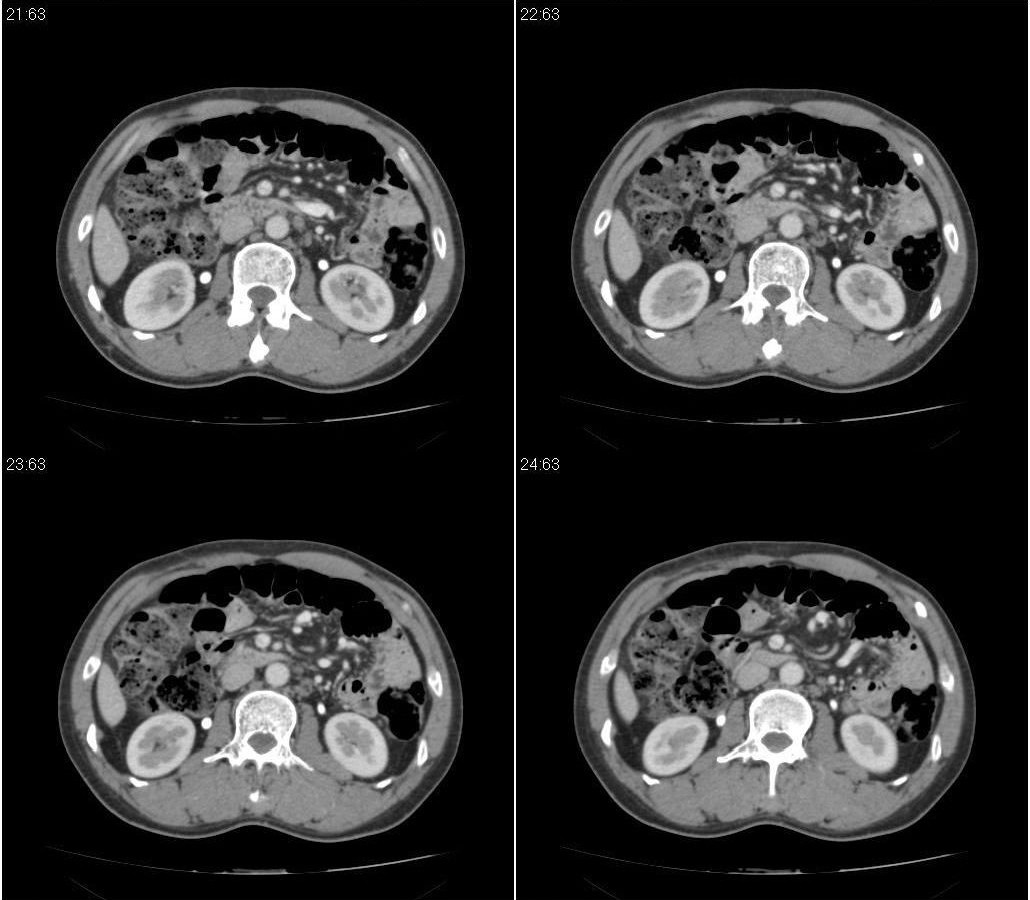

标题: CT21384:男性,50岁。发现无痛性黄疸十余天,B朝提示肝胆管 [打印本页]

标题: CT21384:男性,50岁。发现无痛性黄疸十余天,B朝提示肝胆管

1.考虑:壶腹占位病变(癌?)。

2.胆系低位梗阻:肝内外胆管扩张,胆囊增大,胰管扩张。

胰头癌伴低位胆道梗阻。

胆系低位梗阻(肝内外胆管扩张,胆囊增大,胰管扩张);考虑胰头癌或壶腹癌所致。

胰头强化欠均匀,胆胰管扩张。考虑胰头癌可能性大。

胆系低位梗阻(肝内外胆管扩张,胆囊增大,胰管扩张,钩突似有占位);考虑胰头癌